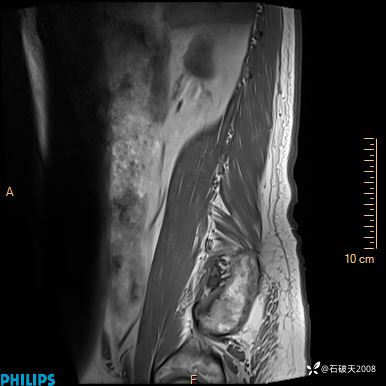

2023年3月份MRI影像

T2矢状位压脂

现病史:7个月前患者因骶尾部占位就诊于北京大学人民医院,MRI示:骶骨右侧及右骶前占位,考虑骨巨细胞瘤可能,动脉瘤样骨囊肿可能,神经源性肿瘤待排。行手术治疗,术后病理回示:XXXXX。术后给予对症治疗,具体不详,恢复良好。近几个月反复出现发热,伴骶尾部不适,多次住院给予对症治疗,2天前患者无明显诱因再次发热伴骶尾部不适,无大小便失禁,为求进一步治疗,遂门诊来我院,在门诊初步检查后,以“骶尾部肿物”为诊断收入我科。入院来患者神志清,精神一般,饮食睡眠可,大小便无明显异常,体重无下降。